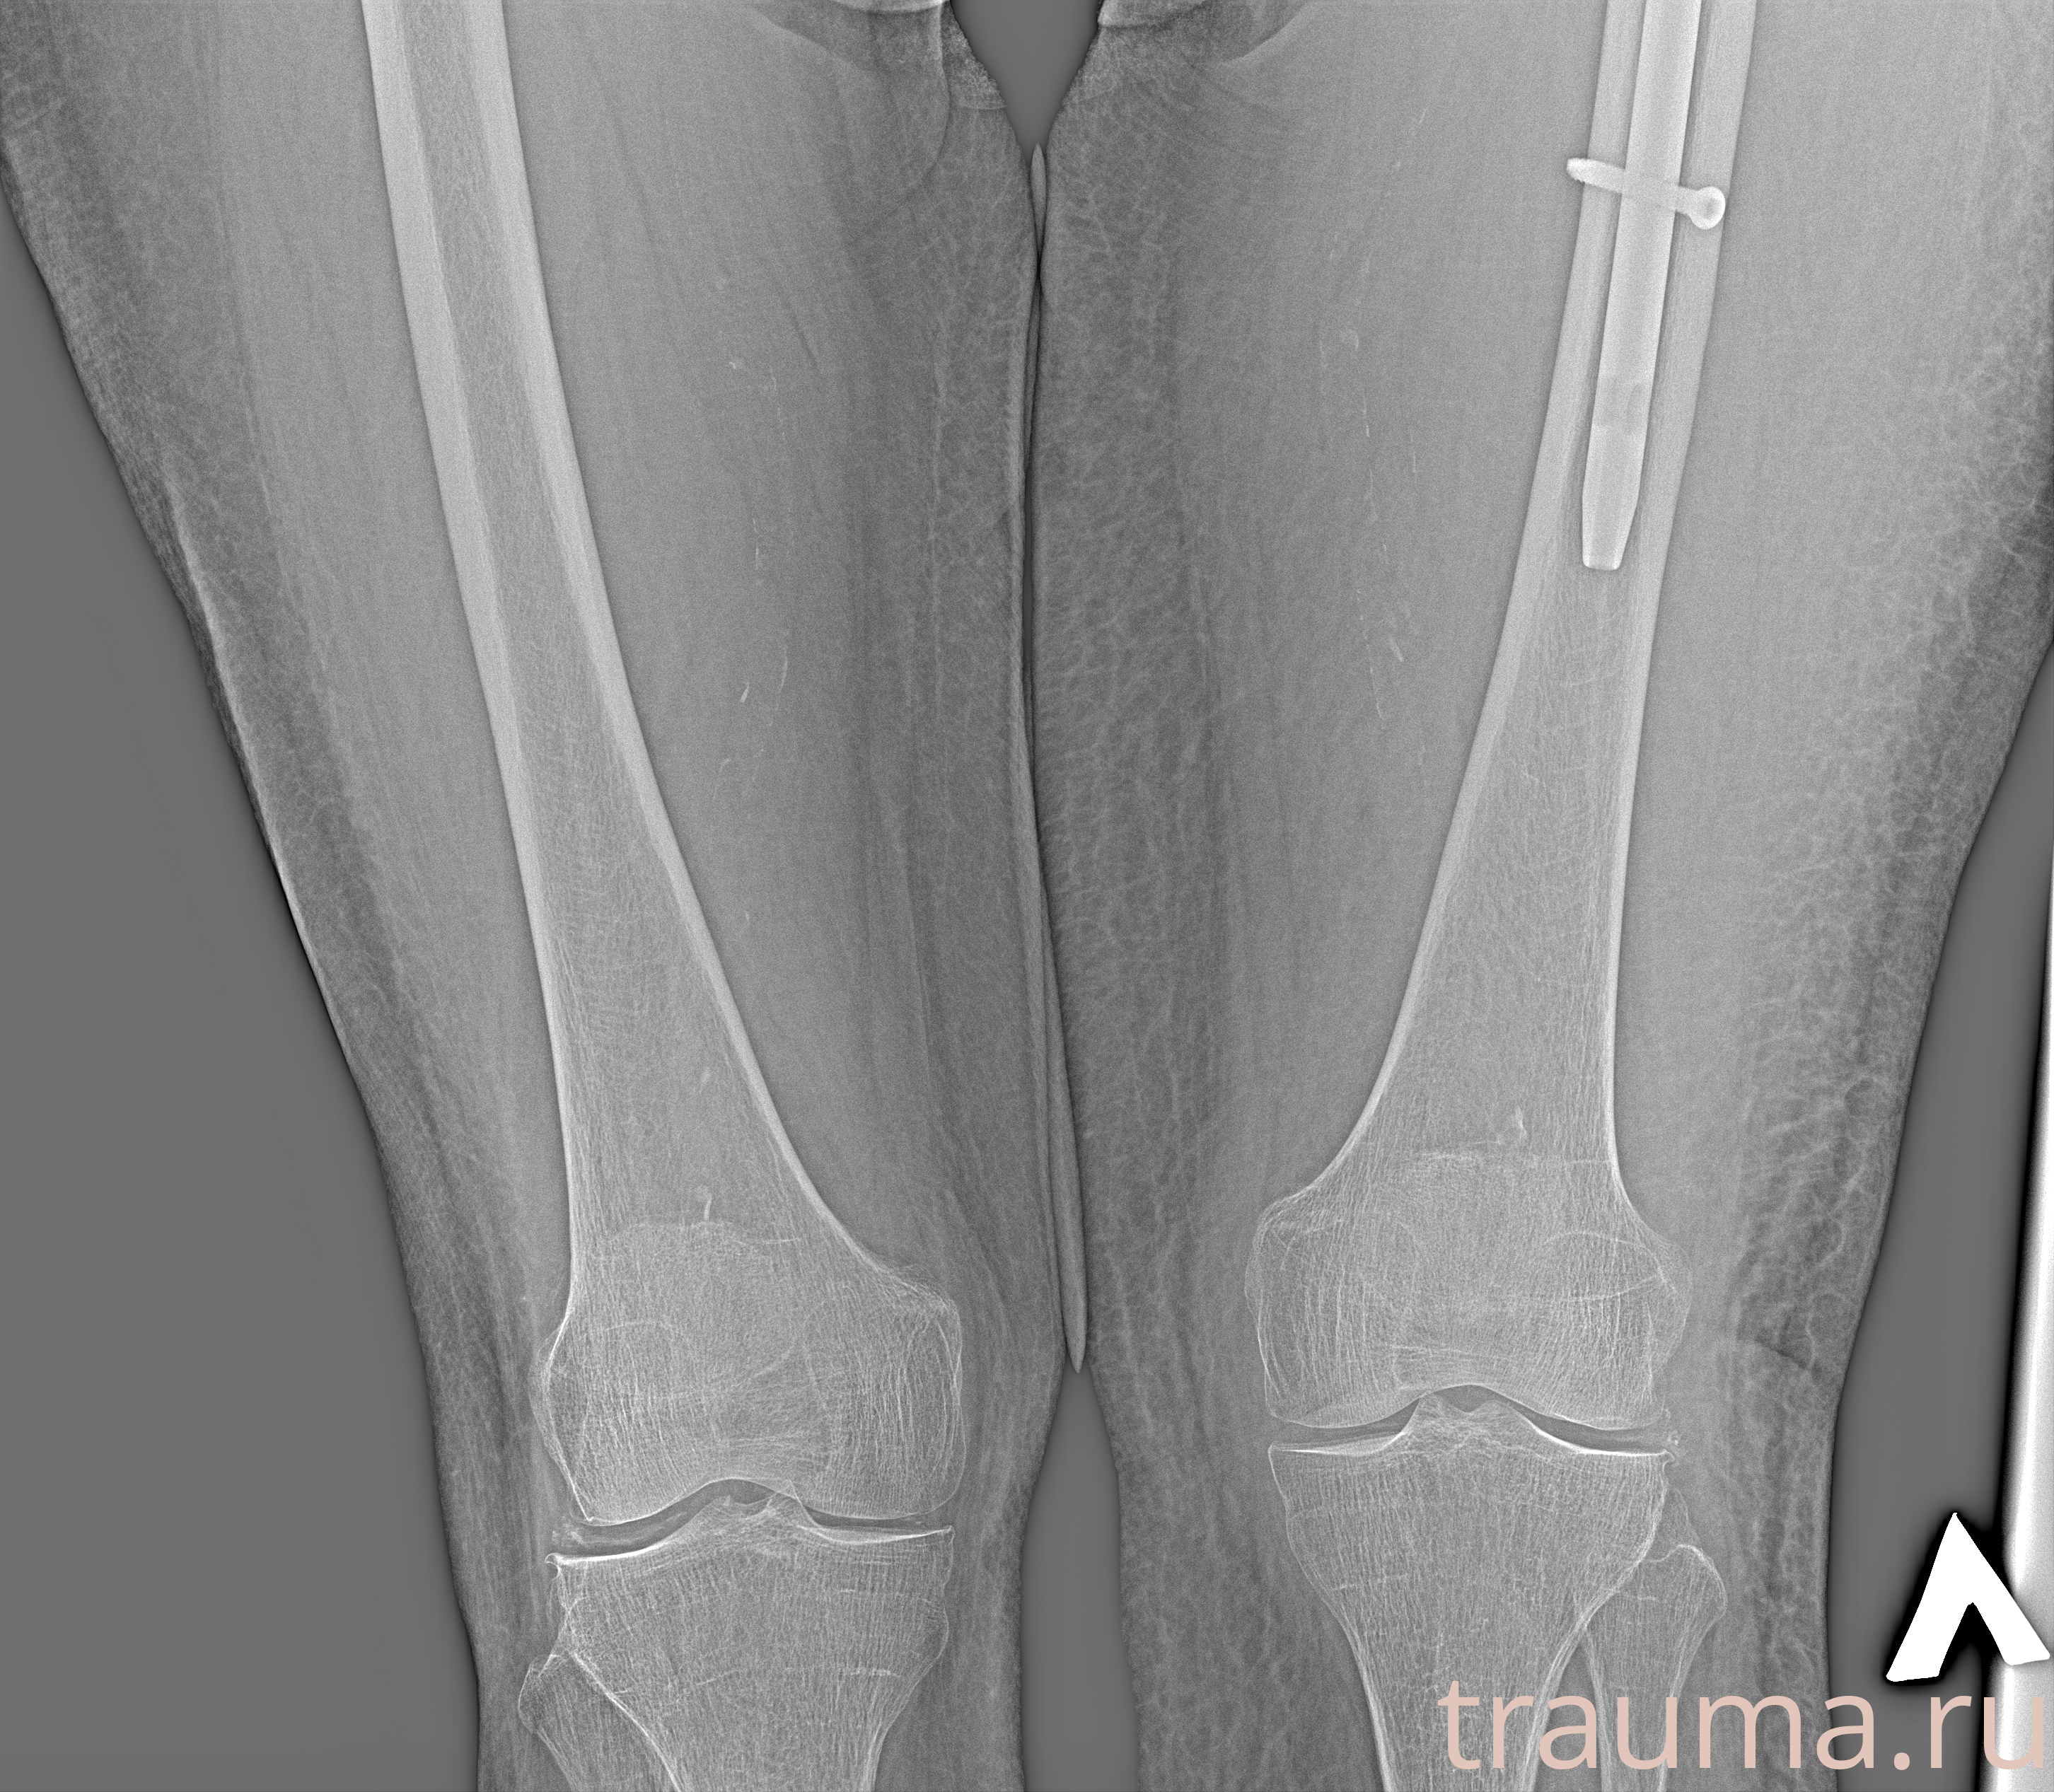

Рентгенограммы

Рентген на дому: по вашему адресу приезжает врач-рентгенолог, травматолог-ортопед с мобильным рентгеновским аппаратом, проводит диагностику травмы или заболевания, делает необходимые рентгенограммы, дает рекомендации по дальнейшему лечению. Получить качественные снимки в домашних условиях возможно благодаря уникальной методике, разработанной МосРентген Центром для института  Склифосовского